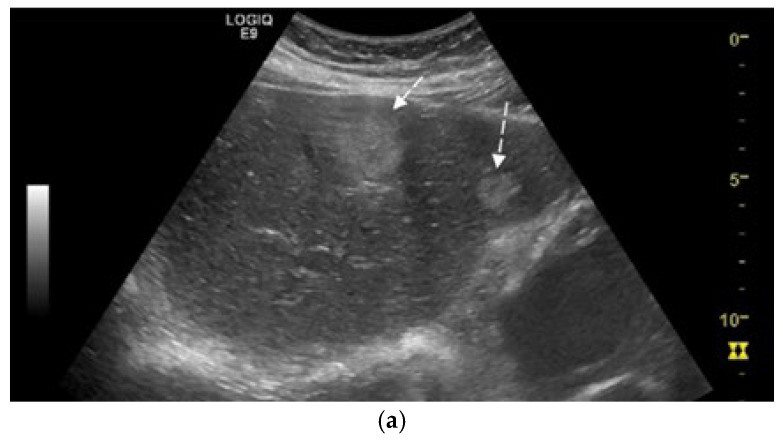

Background and Clinical Significance: Neuroendocrine neoplasms (NENs) are a group of malignancies that may remain clinically silent for many years. The presence of hepatic metastases can be the first clue leading to diagnosis. Case Presentation: We report the case of a 67-year-old man with intermittent tiredness and suspicious hepatic nodules detected on routine abdominal ultrasound. Contrast-enhanced ultrasonography showed arterial hyperenhancement with early washout, suggestive of metastases. Synchronous high-grade neuroendocrine carcinomas (NECs) of the lung and cecum were identified. Although the liver lesions were initially presumed to arise from the cecal tumor, liver biopsy immunohistochemistry was TTF-1 positive/CDX2 negative, whereas the cecal lesion was TTF-1 negative/CDX2 positive. This mutually exclusive immunophenotype confirmed two separate primary carcinomas. Given the high-grade histology, the patient received platinum-based chemotherapy and achieved a partial response. Conclusions: This case illustrates the diagnostic complexity of synchronous lesions and highlights the "mirage of the first lesion" phenomenon, in which the initially detected tumor may not represent the true primary site. A comprehensive, multidisciplinary strategy is crucial for establishing the correct diagnosis and guiding optimal management.